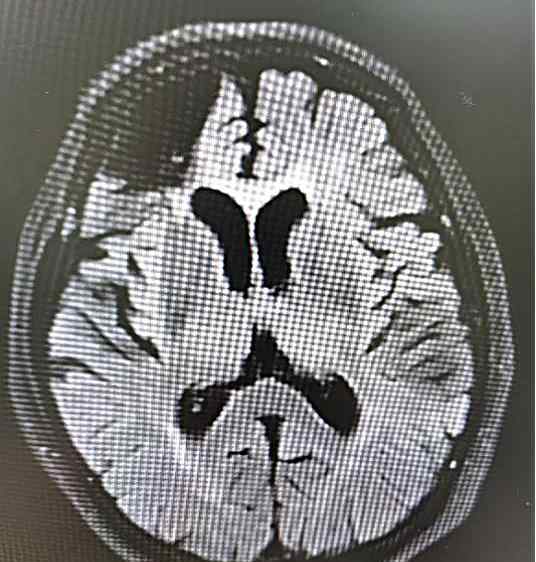

你看头颅MRI多发腔梗灶、严重脑白质变性就是我在王大爷脑子里“后院管理“的结果。

赵阿姨先有脑梗,出现“难伺候”、“疑心病”,就是我入驻了在赵阿姨脑子里,赵阿姨的诊断是脑梗后血管性痴呆,但记性变差,脑MRI显示海马有萎缩,是我携手夫君阿尔茨海默病共同造成的。